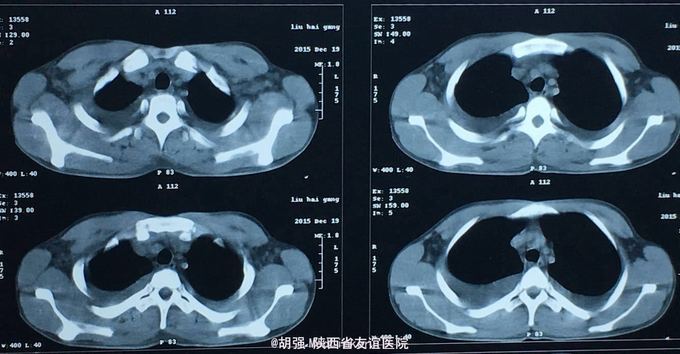

查体:口唇无发绀,咽充血,双侧扁桃体2度大,表面可见脓胎。两肺呼吸音粗糙,可闻及管状呼吸音。余查体无明显异常。 辅助检查:血常规提示白细胞及血小板明显低于正常值,肝功提示转氨酶升高。凝血系列:PT、APTT时间明显延长。T sport试验弱阳性。10月份胸部CT平扫未见明显异常。10月26日及12月12日胸片未见明显异常。12月19日胸部CT提示:两肺斑片状阴影,两侧胸腔积液。